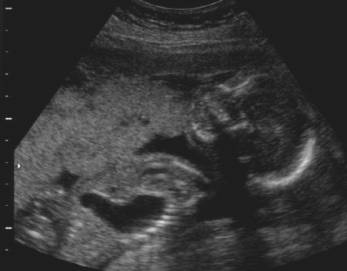

Stomach in left chest cavity

Note the absence of significant cardiac displacement.

This would be unusual in diaphragmatic hernia.